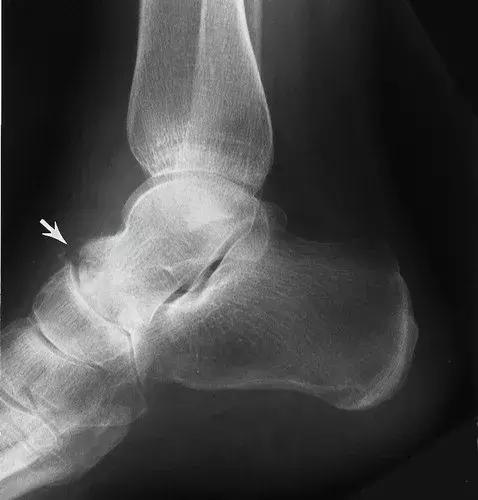

图15:27岁女性糖尿病人,踝关节的神经性骨关节病。侧位X线片显示了大的踝关节积液,其具有碎裂和胫骨关节塌陷(实线箭头)。 存在微血管钙化(空心箭头),表明糖尿病是神经性骨关节病的原因。 虽然不如脚的神经性畸形常见,但糖尿病神经病变患者也会发生神经性踝关节改变。